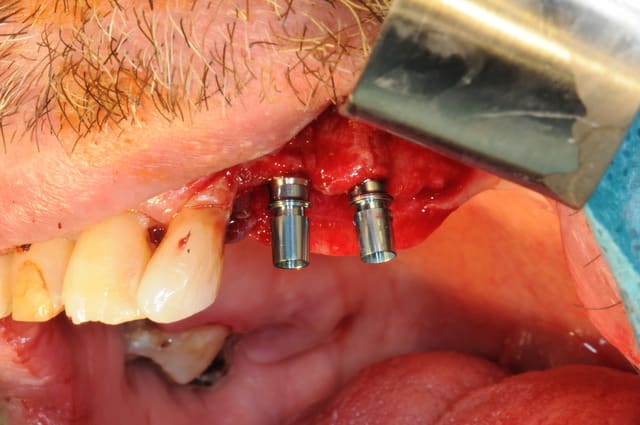

si ça peux alimenter ta réflexion...

manque d'intelligence de ma part j'ai pas fait de photo du cas au tout départ. mais la première photo devrait vous donner une idée du reste...

la suite c'est pose 4 implants, ceramique, stellite sur locators (beaucoup moins couteux qu'une barre et plus facile à nettoyer)